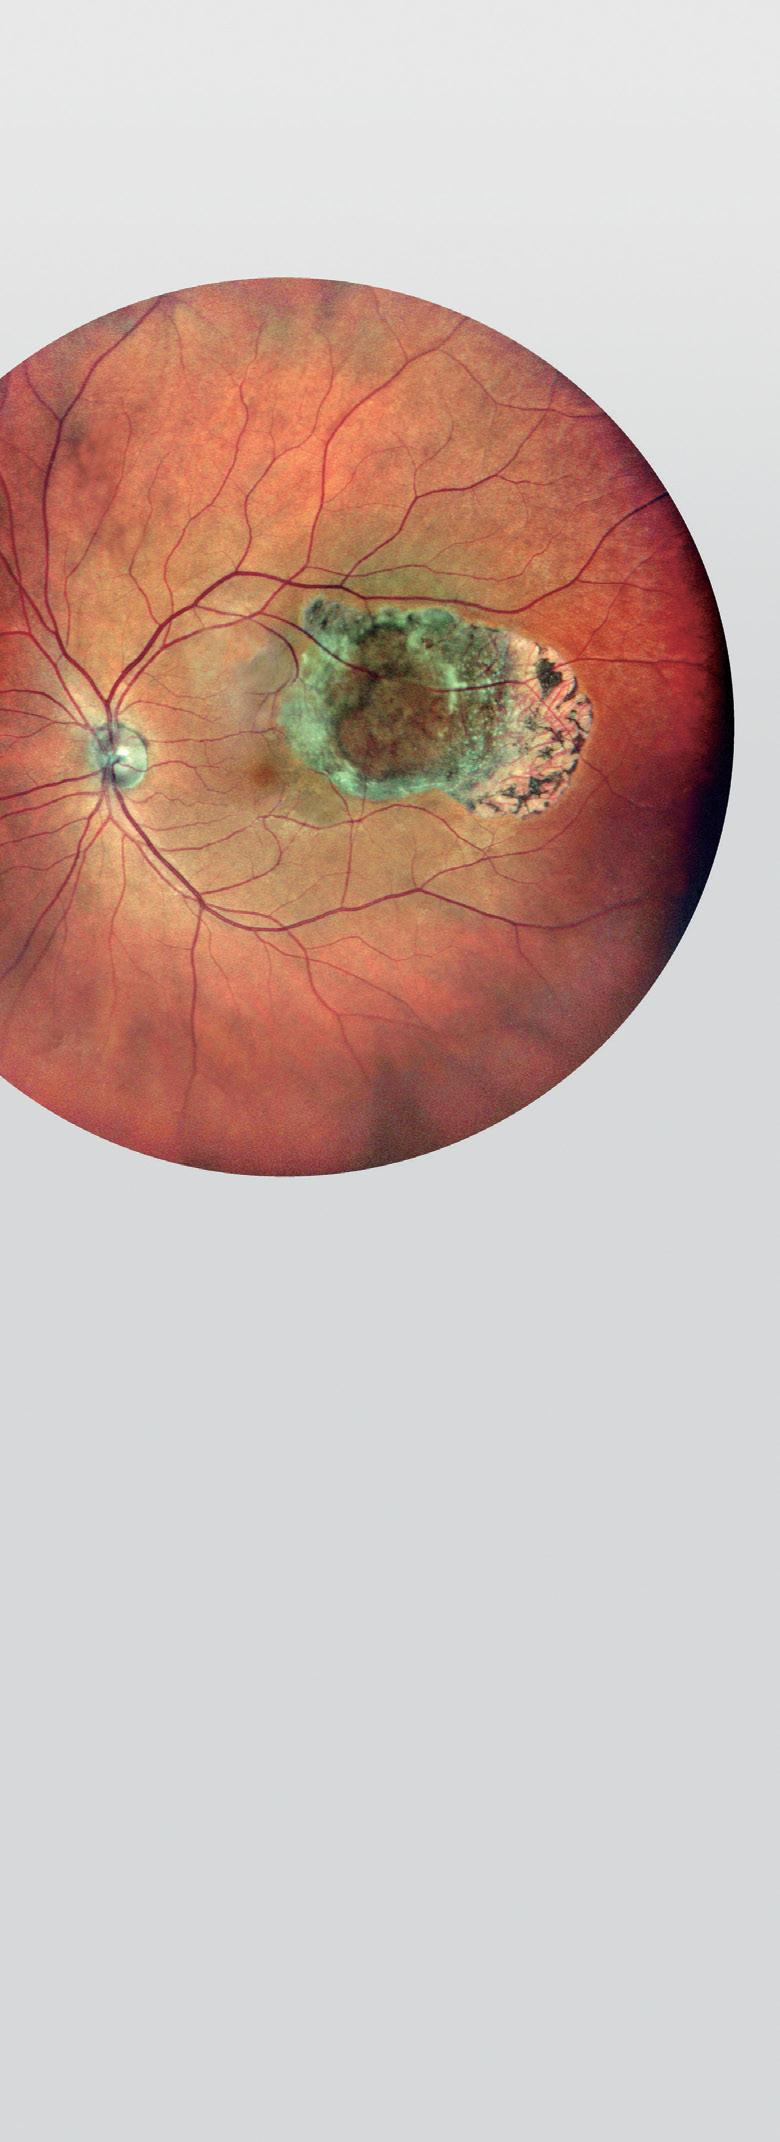

Post-paediatric cataract surgery Glaucoma: A: 3.5 years old child with cataract surgery done in infancy. Glaucoma with enlarged corneal diameter and a dislocated IOL are seen. One previous Ahmed glaucoma valve (AGV) in supero-temporal quadrant has failed to control IOP adequately; B: A second AGV plate is sutured in the infero-temporal quadrant. A closed chamber vertical translocation of haptics to glued IOL is then done sitting temporally, taking advantage of smaller vertical diameter of cornea; C: Adequate length of the externalised haptics of the IOL is seen; D: Haptics are tucked in. A well-centred IOL is seen. The AGV tube tip is positioned posterior to the iris in front of the IOL. Adequate vitrectomy is performed during IOL translocation as well as after inserting the tube tip